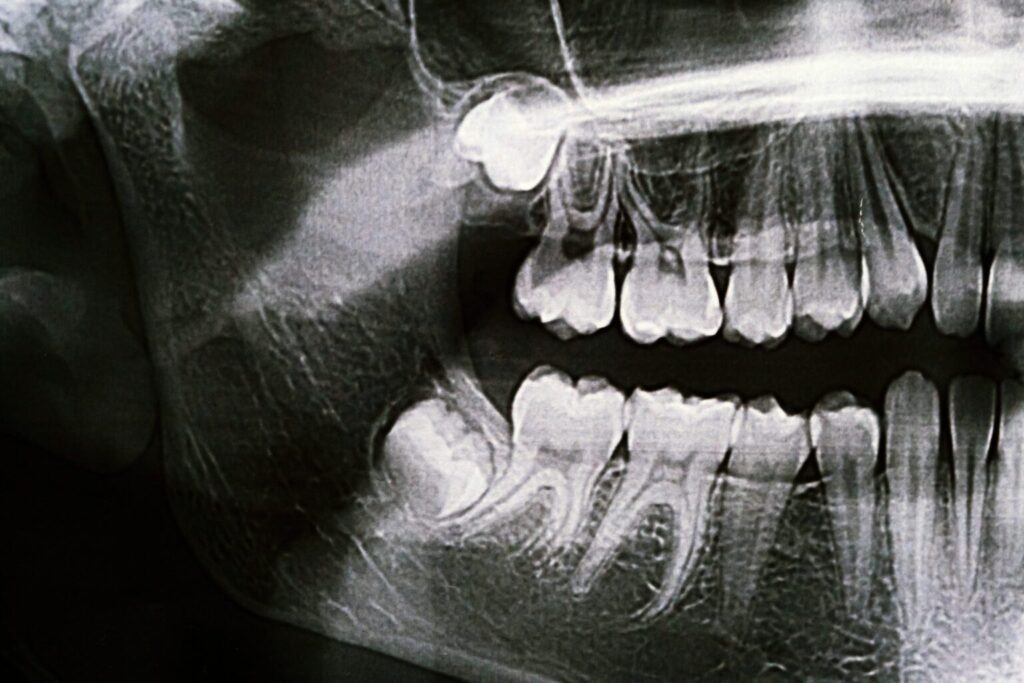

The human jaw has evolved to be smaller over time, which means many people don’t have enough space to accommodate wisdom teeth. When there isn’t sufficient room, these teeth can become impacted, meaning they are unable to fully emerge through the gums or grow in at odd angles. Common problems associated with wisdom teeth include:

• Impaction: The tooth is trapped beneath the gum or grows sideways into adjacent teeth.

• Cysts: Fluid-filled sacs can form around impacted teeth, potentially damaging bone and roots.

At Cameo Dental Specialists, we use cone beam 3D imaging to assess the position of your wisdom teeth and evaluate their impact on surrounding structures. This advanced technology allows us to plan your procedure with precision.